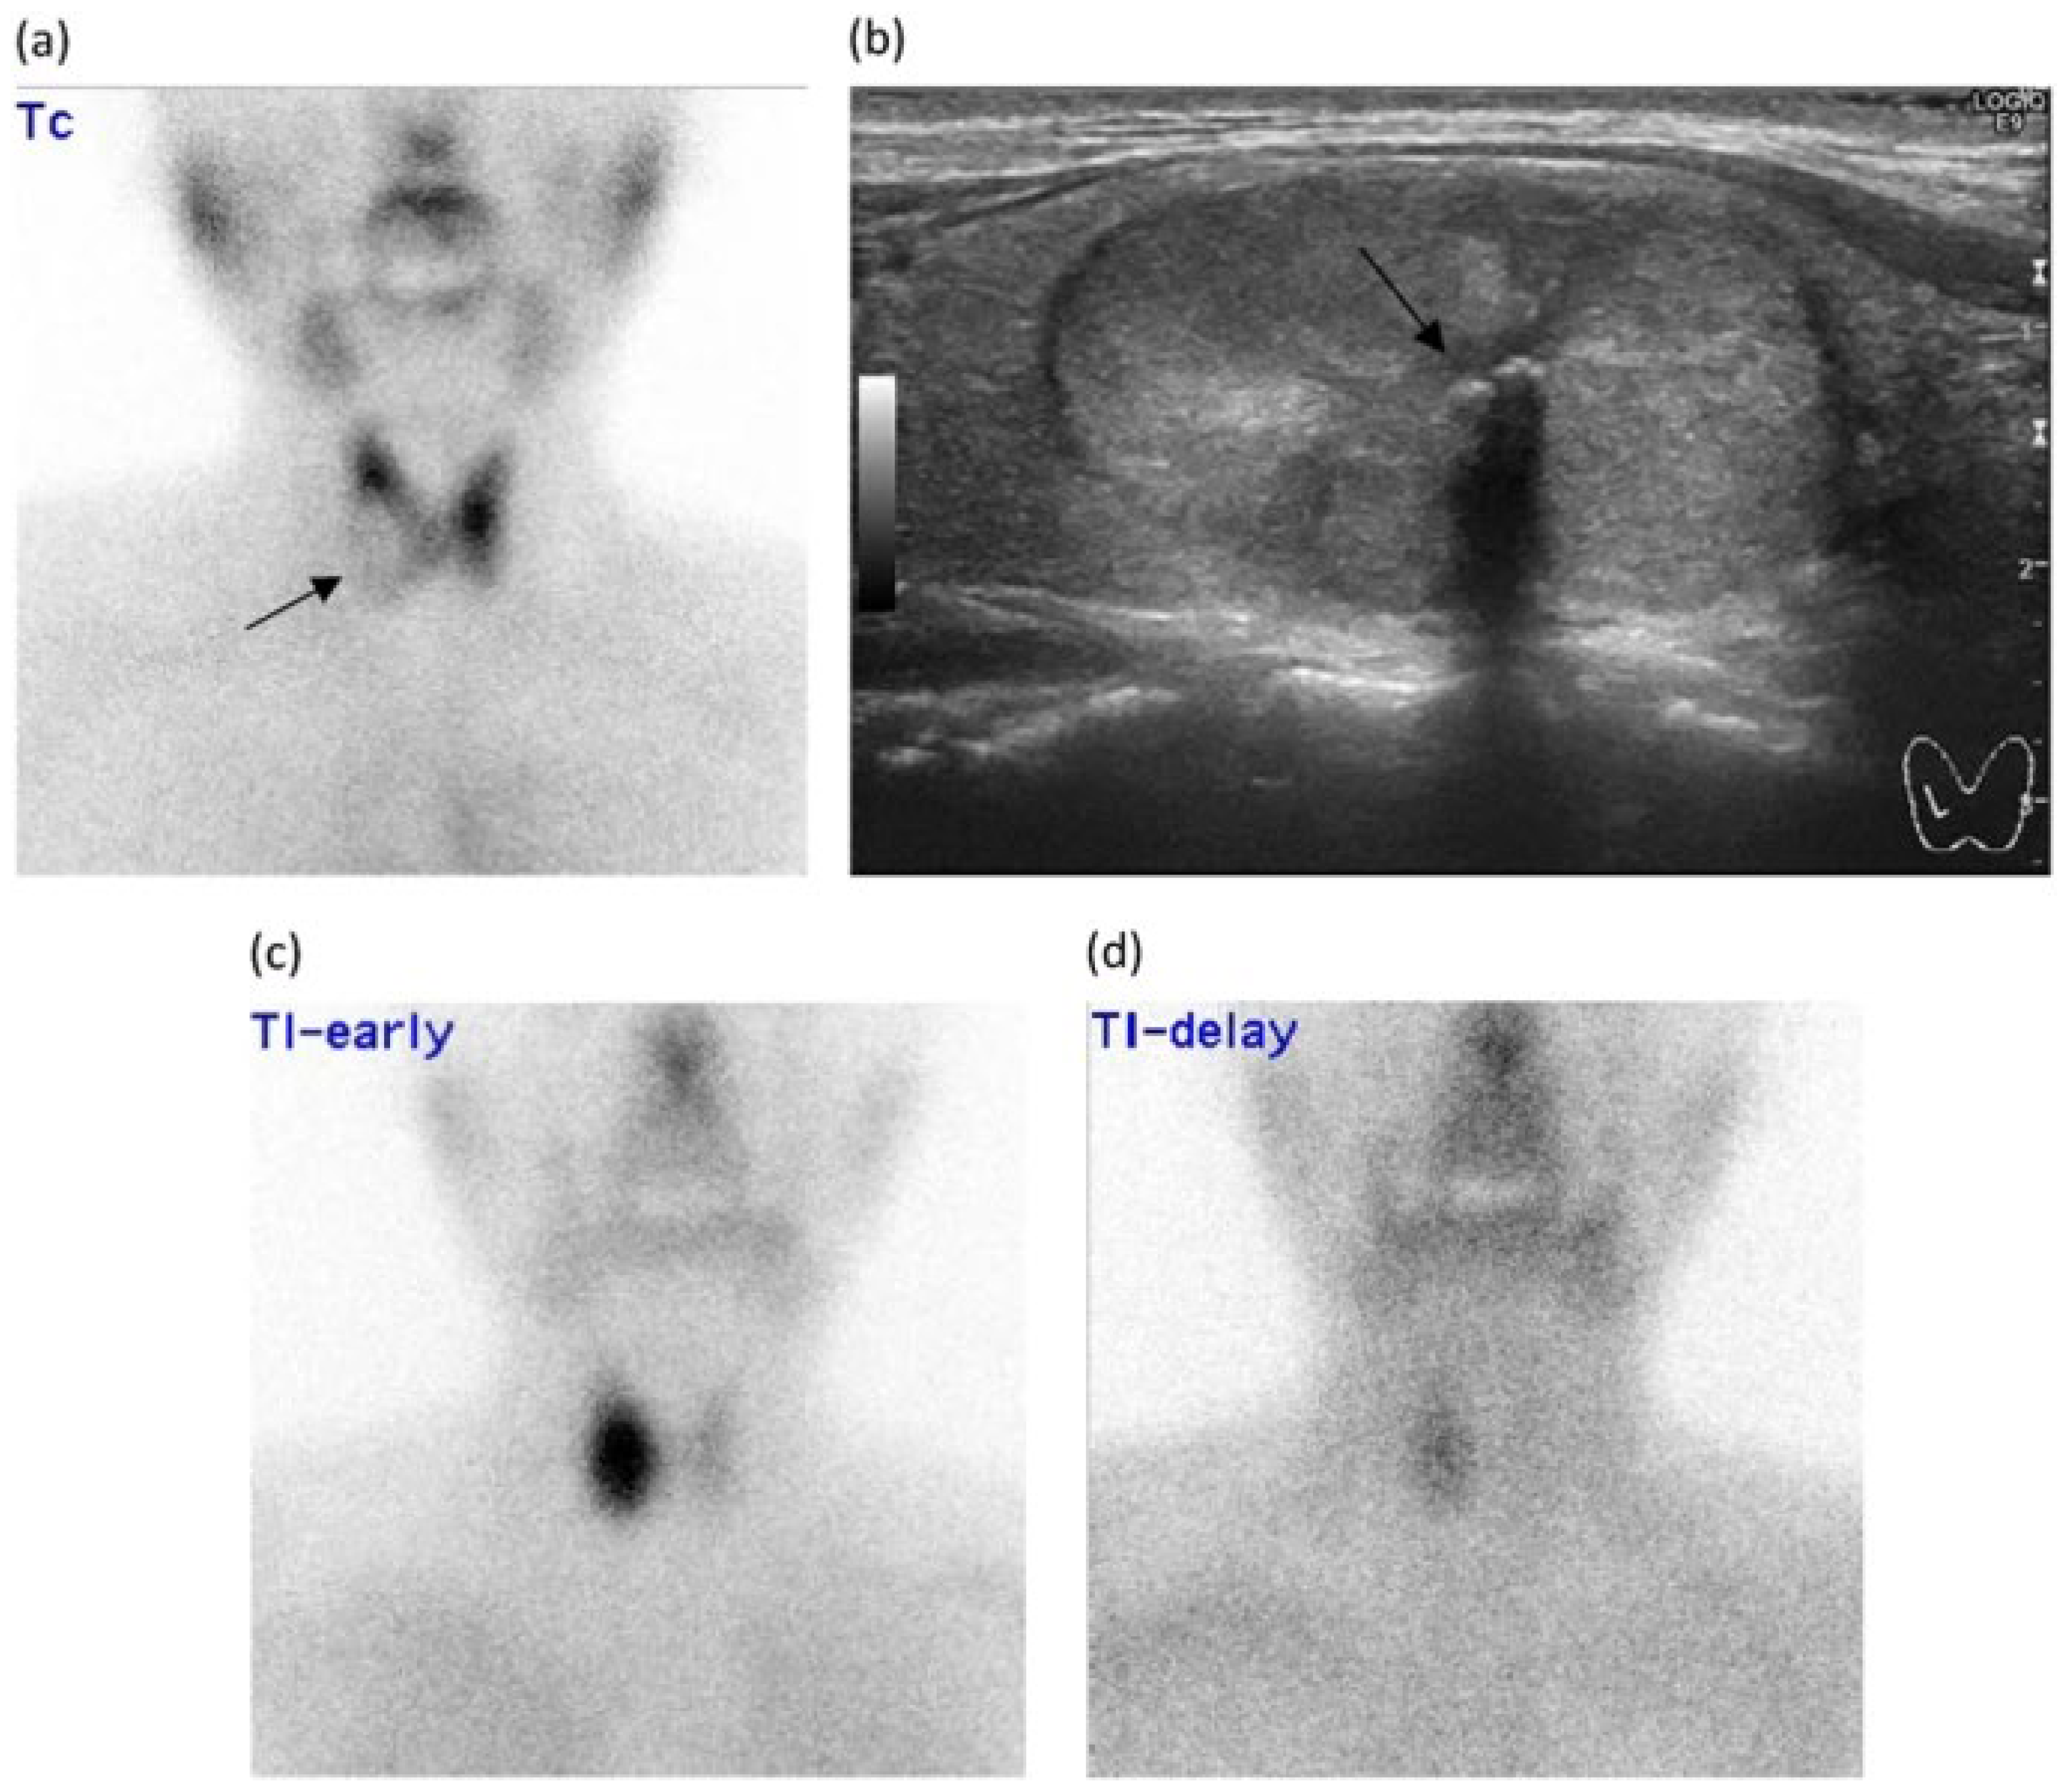

- Watanabe, K.; Igarashi, T.; Ashida, H.; Ogiwara, S.; Ohta, T.; Uchiyama, M.; Ojiri, H. Diagnostic value of ultrasonography and TI-201/Tc-99m dual scintigraphy in differentiating between benign and malignant thyroid nodules. Endocrine 2019, 63, 301–309. [Google Scholar] [CrossRef]